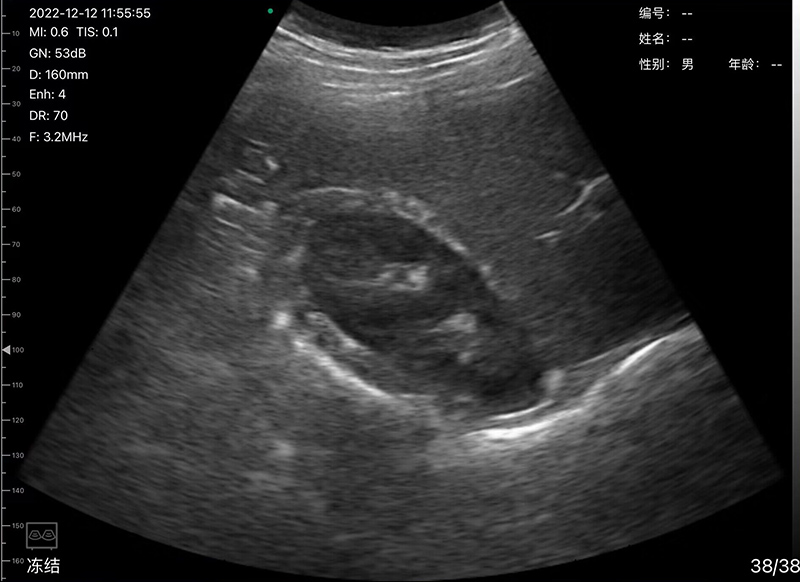

• Scan mode: Electronic Array Convex scanning

• Frequency: Convex probe 3.2/5.0MHz

• Display mode: B, B/M, Color, PDI, PW